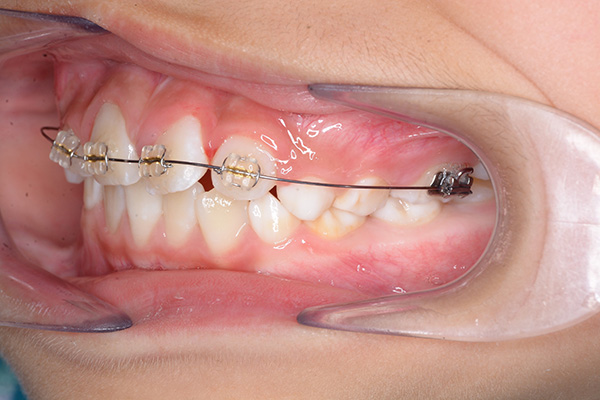

| 主訴 | 上顎前歯のでこぼこ | 診断名 | アングルⅡ級叢生症例 | ||||

|---|---|---|---|---|---|---|---|

| 初診時年齢 | 6歳9ヵ月 | 性別 | 男 | 動的治療期間 | 6ヵ月 | ||

| 使用装置 | 0.018" × 0.025" standard edgewise | ||||||

| 既往歴として上顎正中過剰歯(2本)は抜去済み。その影響で上顎右側中切歯は捻転して萌出しており、下顎右側中切歯と早期接触が認められたため2x4(上顎のみブラケット装着)にて前歯部の改善を行った。現在は永久歯列完成まで経過観察を行い、希望があれば口元の突出感を改善するために本格矯正治療を行うことにしている。 | |

| 批評・予后 | 早期治療によって前歯部の咬合干渉は回避され、その後の永久歯への交換は順調である。 |